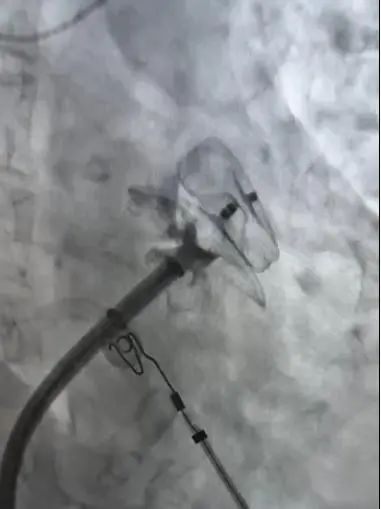

释放后的左心耳封堵器

手术在西安交通大学第二附属医院王洪涛教授的指导、何丽团队及超声科罗利红主任团队、相关科室的配合下开展。在确认患者心耳内无血栓的情况下,手术团队结合食道超声和CTPV术前结果,在完成环肺静脉隔离后,选择合适左心耳封堵器,一次展开即完成封堵,两种术式实现无缝衔接,手术用时约2个钟头。在医务人员的精心照护下,患者目前恢复良好。